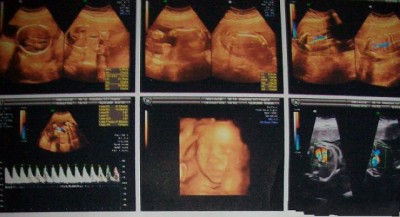

现在胎宝宝身长16~18厘米,重300~500克。这时期,胎儿的体重开始大幅增加,眉毛和眼脸清晰可见,手指和脚趾也开始长出指甲。如果胎儿是个女孩,她的阴道现在已经形成了,并且会继续发育到出生;如果是男孩,*丸睾**将从盆骨降到阴囊内,原始精子已经形成。随着大脑和神经末梢的发育,胎儿的各种感官正在逐步完善,如味蕾开始在舌面上形成。

本周胎儿重350克左右,身长达到了19厘米左右。胎宝宝的脑部开始迅速生长,尤其是位于大脑中心的生发基质,它负责产生脑细胞。胎儿现在看上去滑溜溜的,胎脂覆盖了他的全身。胎脂可以保护胎儿的皮肤,不少胎儿在出生时身上都还残留着这些白色的胎脂。宝宝清醒的时间越来越长,当他清醒时,能够很清楚地听到外面大人的谈话、音乐或噪音。有时孕妈妈轻轻拍打腹部时,他也会被惊醒。

本周胎儿大约重450克,从头到臀长20厘米左右。这时期,胎儿的皮肤薄薄的,红红的,还皱巴巴的,样子像个小老头,但身体比例已经较为匀称。胎儿的嘴唇、眉毛和眼睫毛已清晰可见。宝宝的眼睛已经发育,视网膜也已形成,具备了微弱的视觉。宝宝的嘴唇越来越清晰,在胎儿的牙龈下面,幼小的牙蕾也开始发育了,显露出长牙的最初迹象。

怀孕第24周